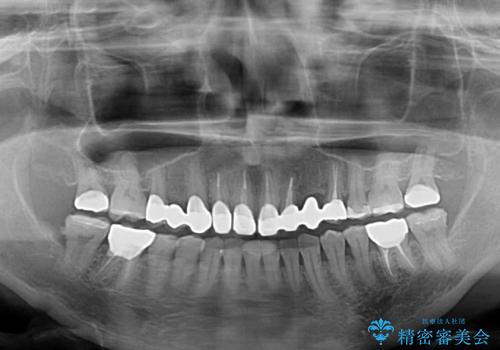

- 他院で矯正治療を終えたものの、むし歯や欠損部の治療が進められないとのことで来院された患者様です。

欠損部や、銀歯やむし歯の大きな歯はセラミッククラウンやブリッジに、小さいむし歯はセラミックインレーにて治療を行うこととしました。